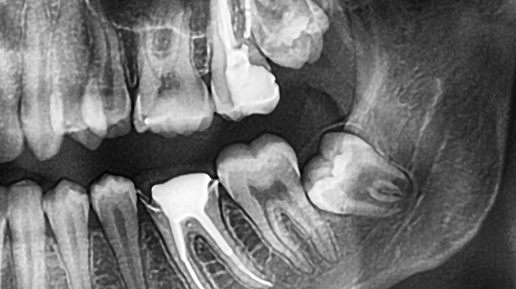

Зубы мудрости — пожалуй, самые загадочные в нашем организме. Они появляются последними, когда челюсть уже сформирована, а места для них часто почти нет. У кого-то «восьмёрки» растут без проблем, у других приносят боль, воспаление и требуют удаления. Почему так происходит и когда действительно нужно прощаться с зубом мудрости — рассказывает стоматолог. Зубы мудрости — это третьи моляры, расположенные в самом конце зубного ряда. Обычно они появляются в возрасте от 17 до 25 лет, но у некоторых — позже или вовсе не прорезываются...